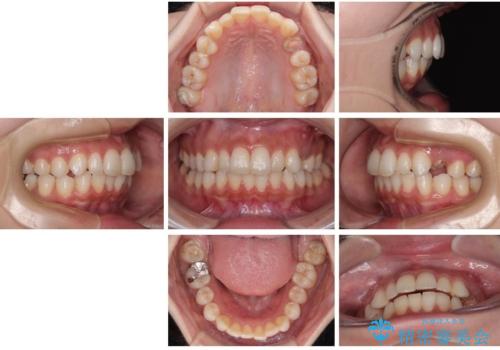

左上の小臼歯は健全な歯質が薄く将来的な歯根破折リスクが高く予後不良で、叢生(歯並びの乱れ)はほとんどなくご本人も歯並び自体は気になっていないという状態でした。

左上小臼歯を抜歯し、矯正治療でスペースを閉じる方法と左上小臼歯を抜歯し、抜歯即時インプラントを行う方法、保存療法を行う方法の治療期間、費用、メリット・デメリットについて説明したうえで治療期間をできるだけ短くしたいという希望があったため抜歯即時インプラント治療を選択されました。

矯正・インプラント・保存治療を含めた総合的な診断によって、患者様に合った選択肢が見つかることがあります。

治療法は一つではありません。お悩みの方は、ぜひ一度ご相談ください。